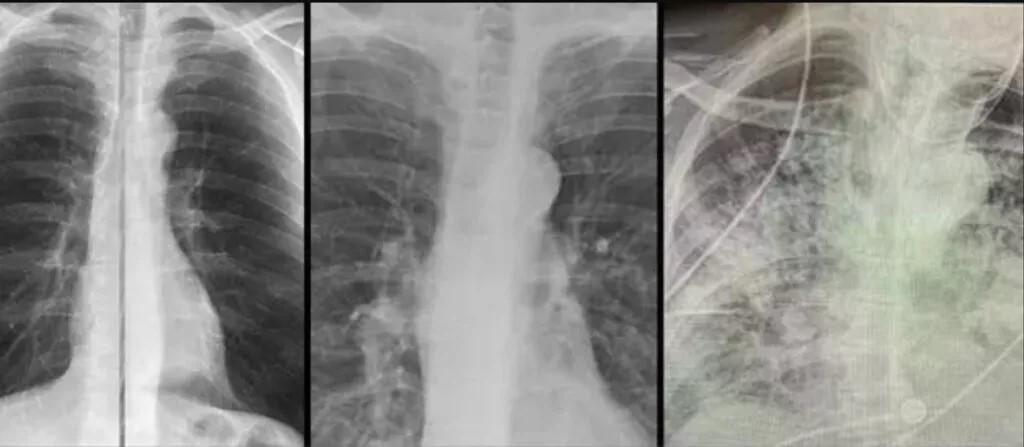

Karşılaştırılan röntgen sonuçları büyük dikkat çekti. En soldaki görselde sigara içen bir bireyin akciğer filmi görülürken sağdaki filmde ise Kovid-19’u yenmiş bir bireyinki bulunuyor.

Akciğer filminde siyah alanlar ne kadar fazla ise o kişinin ciğer kapasitesi ve sağlığı o kadar iyi demektir. Beyaz kısımların artması ise akciğerin kapasitesinin azaldığı anlamını taşır.

Karşılaştırılan röntgen sonuçlarıyla Kovid-19’u geçirmiş ve sağlığına kavuşmuş kişilerin ciğerlerinde görülen hasarın sigara bağımlısı olan kişilerden çok daha kötü olduğunu gözler önüne seren Bankhead-Kendall, ‘Sağlıklı bir bireyin röntgen sonucunda siyah alan büyük olur. Bu da o kişinin ciğerlerine alabileceği oksijen seviyesini gösterir.

Sigara içenlerde hafif hareler yer alırken Covid-19 hastalarının ciğerleri ise bembeyazdır. Yani bu da koronavirüsü yenenlerde bile akciğer sorunları yaşanabildiğini gösteriyor’ açıklamasında bulundu.

Bankhead-Kendall, karşılaştırma yapabilmek için sağlıklı bir bireye ait olan akciğer filmini de paylaştı. Kovid-19’u atlatan kişilerin nefes almakta sıkıntı yaşayabileceğine vurgulayan Bankhead-Kendall, sosyal medya hesabından, ‘Bunu kimin duyması gerek bilmiyorum fakat koronavirüsü geçirmiş bir kişinin akciğerleri, yıllarca sigara içmiş bir tiryakinin ciğerlerinden çok ama çok kötü. Bu insanlar bayılıyor, nefesleri kesiliyor ve benzeri birçok sorun yaşıyorlar’ dedi.